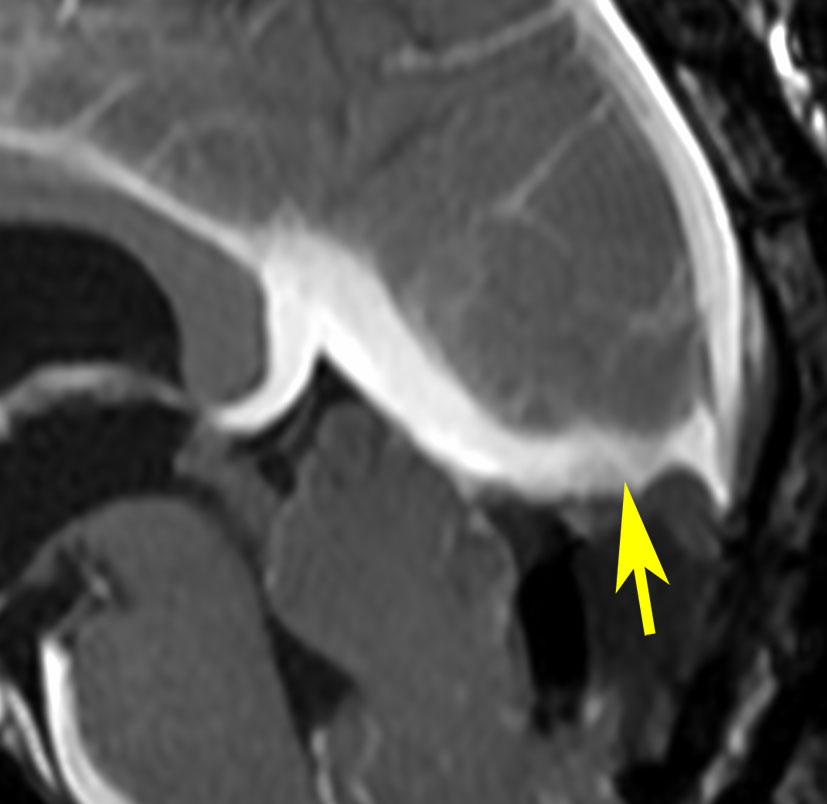

若い女性に偶然発見されたものです。直静脈洞と静脈洞交会の接合部あたりに発生したもので,静脈洞はほぼ閉塞に近い所見でした。しかし,この部分の静脈洞は,テント硬静脈側副路が発達することがあるので,硬膜を含めた積極的な摘出をすることは絶対にできません。もしほんの少しでも流れがある直静脈洞を閉塞させると短時間に脳死になるような脳静脈圧亢進が生じる可能性があるからです。静脈洞内に少し取り残して(右下の矢印)手術を終了しました。手術後には定位放射線治療を行って再増大を防ぎます,